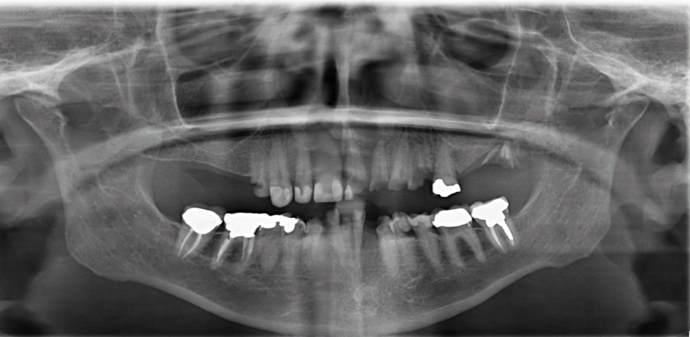

This retired professional had really healthy teeth until she was placed on several medications which caused dry mouth and quickly deteriorated her teeth beyond repair. She was extremely dissatisfied with her smile and wanted the best possible result. She had been offered snap on implant dentures by multiple dentists but she disliked the idea of removing her teeth at night and was therefore treated with full arch fixed bridges supported by implants all done in one day!

Procedures : extractions, implants, All on 4 , Teeth in a day, no bone grafting and full mouth reconstruction with monolithic zirconia bridges.